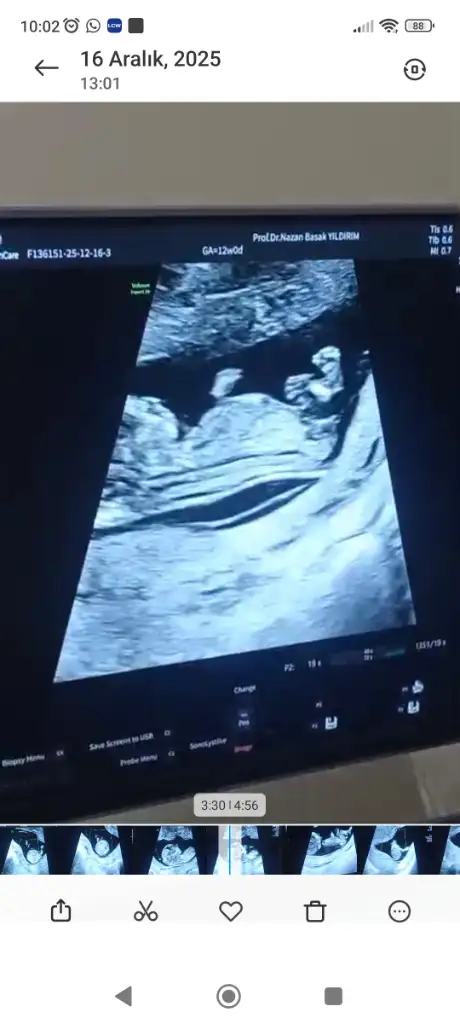

12+0 da doktor kontrolünde ilk kız bebek dedi sonra erkek dedi sonra emin olamadım 16 haftada kesinleetireyim dedi anlayan varsa yorum yapabilir mi

• Screenshot_2025-12-16-15-35-25-067_com.miui.gallery.webp

Screenshot_2025-12-16-15-35-25-067_com.miui.gallery.webp

15,9 KB · Görüntüleme: 5